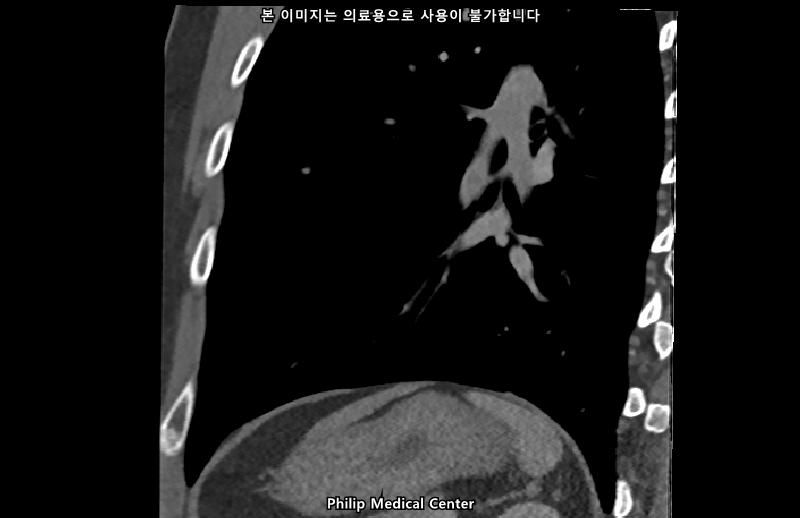

• 1번 째 사진

• 올리신 사진들을 통해서는 폐를 평가할 수 없습니다.

우측 폐첨부에 경미한 섬유성변화와 우중엽에 약 3mm크기의 결절이라는 것은 이상 소견이긴 하지만 보통 경과관찰을 하는 소견입니다.